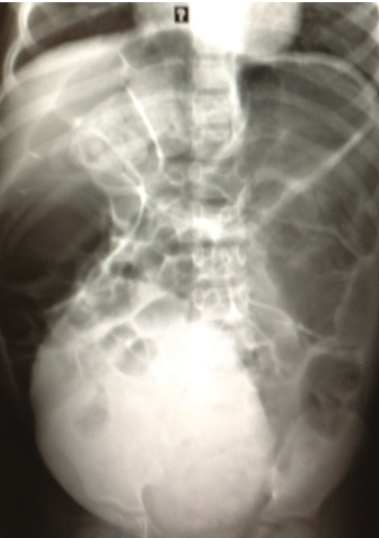

Nisha Polavarapu, MD; Noah Kondamudi, MD, MBA

A 4-year-old boy with chronic constipation presented to the pediatric emergency department with abdominal pain and no bowel movement for 4 days.